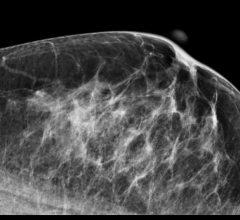

Despite decades of progress in breast imaging, one challenge continues to test even the most skilled radiologists ...

November 10, 2016 — Each year around a million women in the Netherlands undergo mammograms for early detection of ...

The recall rate of screening mammography is reduced when radiologists compare with more than one prior mammogram, a study published in the October 2016 issue of the American Journal of Roentgenology said.

Volpara Solutions announced the launch of a support program to help accredited breast imaging centers across the United States prepare for compliance to the U.S. Food and Drug Administration’s (FDA) Enhancing Quality Using the Inspection Program (EQUIP) initiative. The Volpara "EQUIP-ready" program — which includes draft processes, procedures and forms designed to help users accelerate their compliance efforts — is included with the company's Volpara Enterprise cloud-based quality assurance solution.